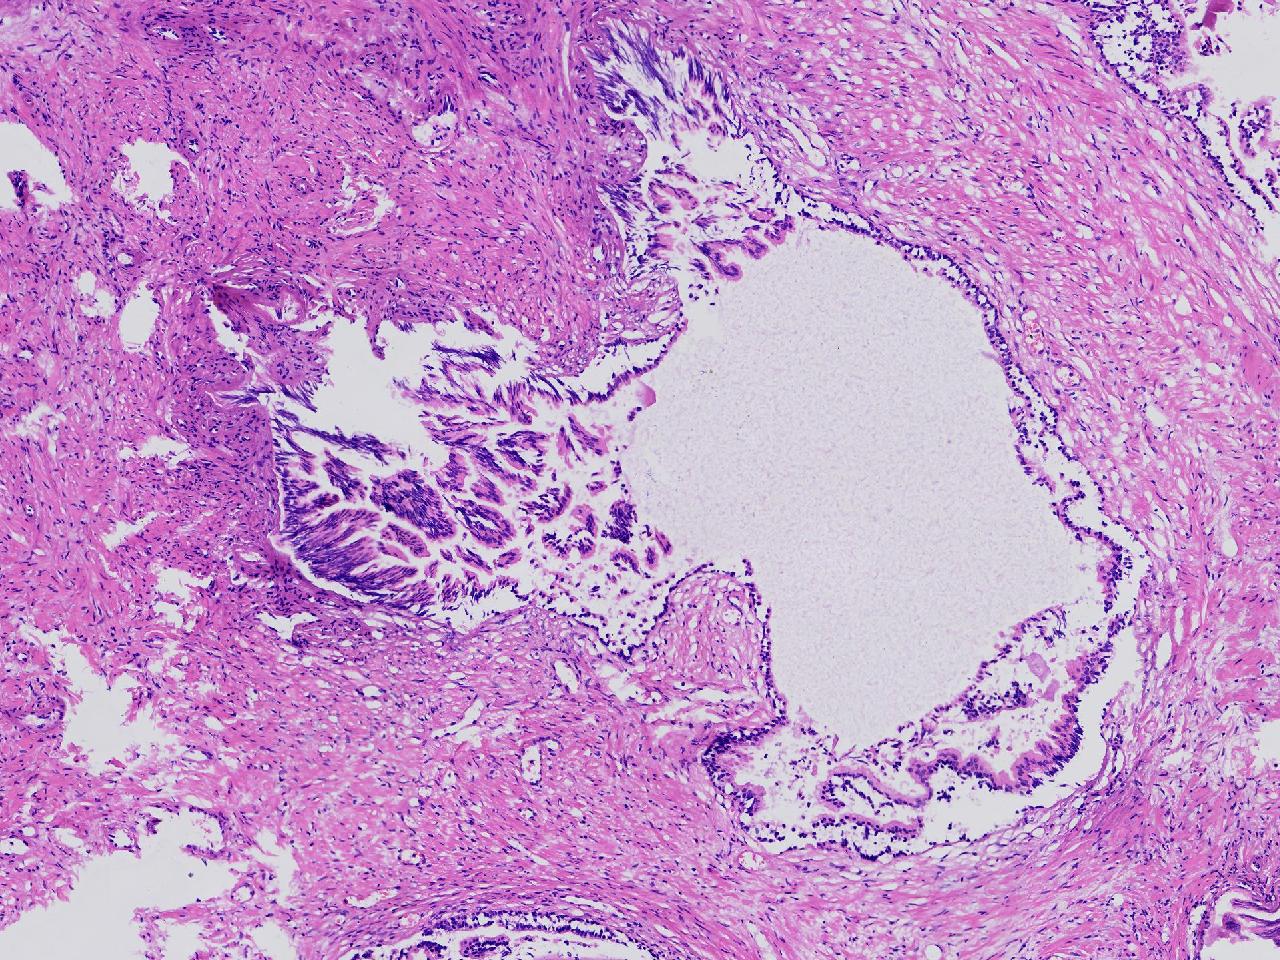

良性前列腺增生?

男,68岁,排尿困难半年余。行前列腺前切术。

前列腺电切标本

灰粉色条索状软组织多块,4X3X3厘米。

考虑为良性前列腺增生症

良性增生

BPH.